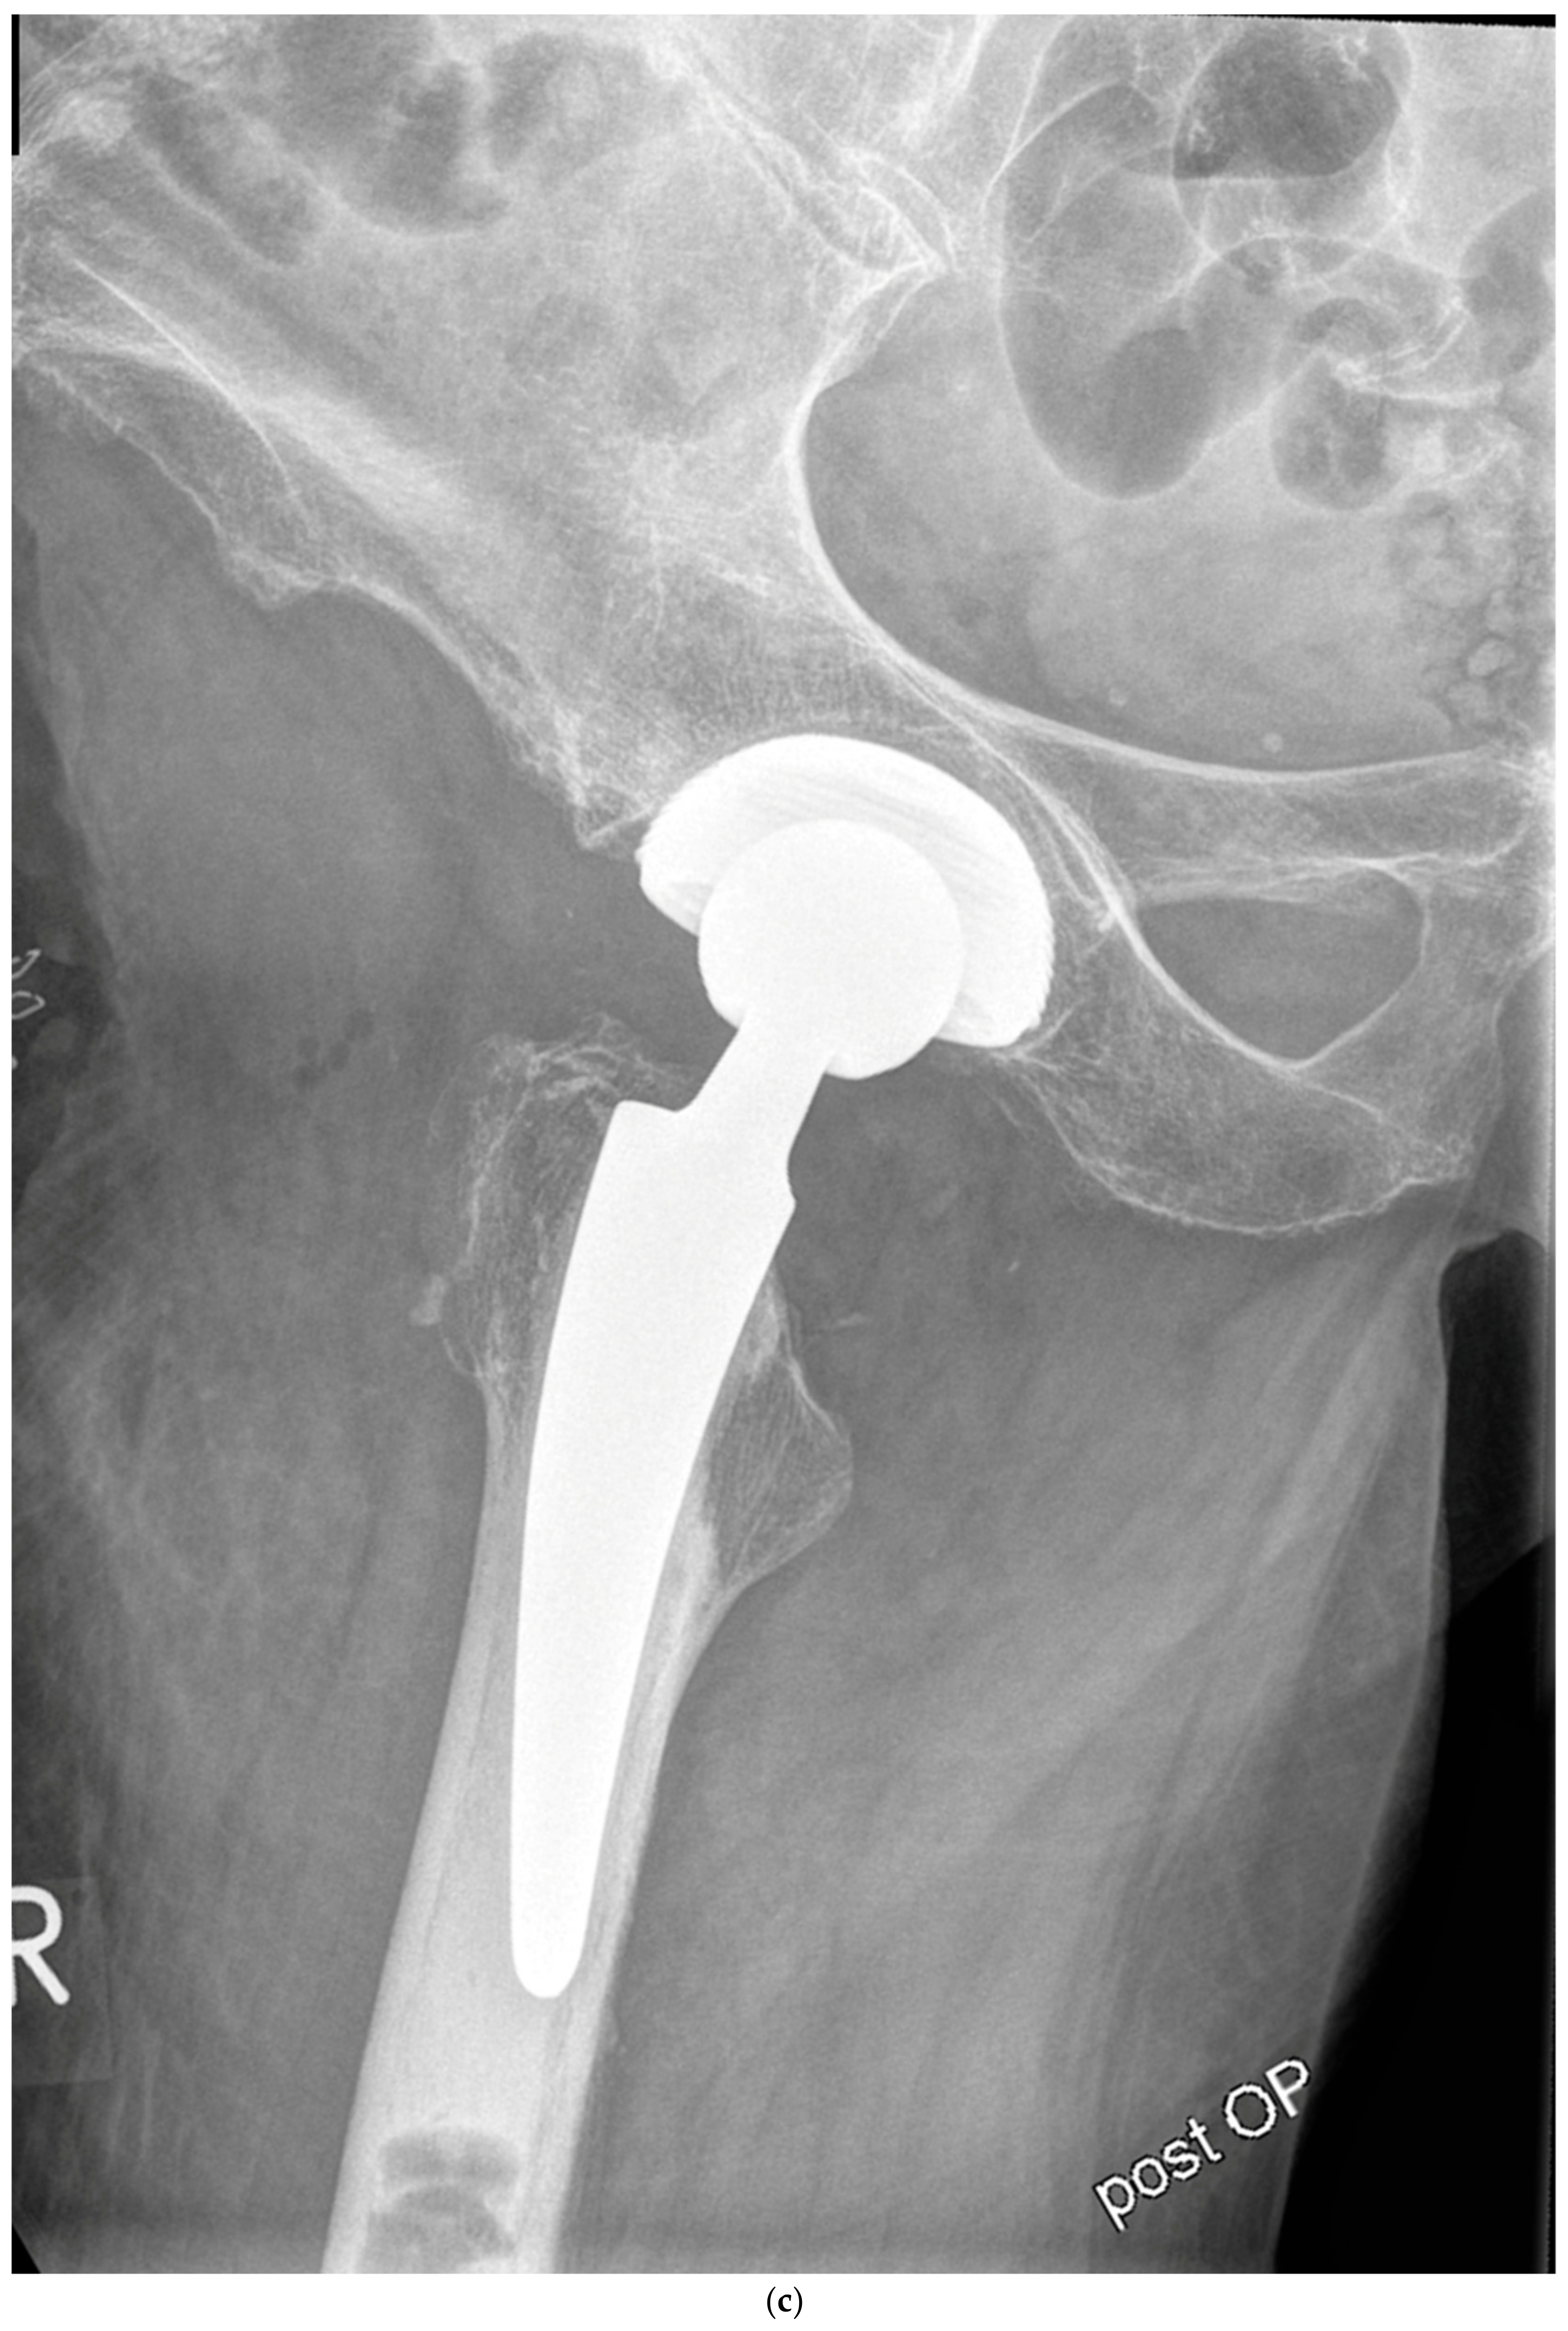

Figure 4.

(a) Case #3: Osteoarthritis, female, 81 years old, preoperative planning. (b) Correct implant position 1 week postoperatively. Homogeneous cement mantle.